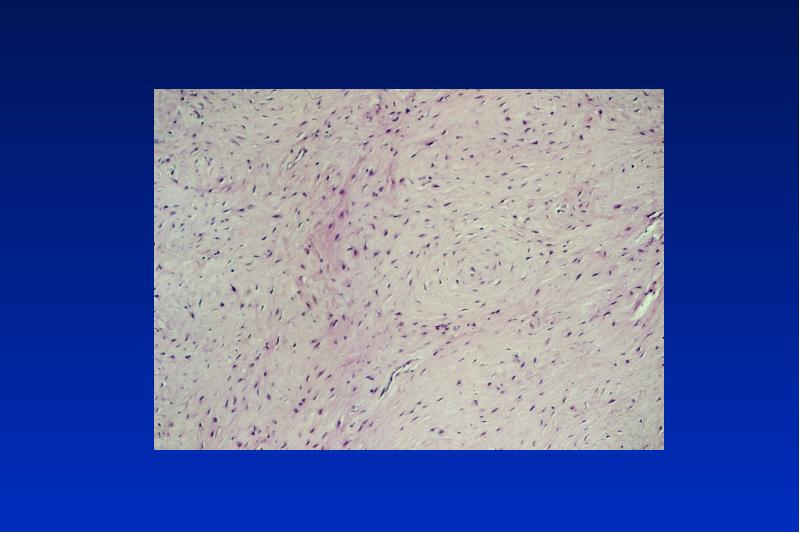

- 63. Myxom lokal invasiv wachsender ectomesenchymaler Tumor ohne Kapsel multilokuläre Osteolyse (Seifenblasen)